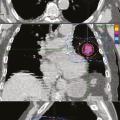

Tableaux et figures